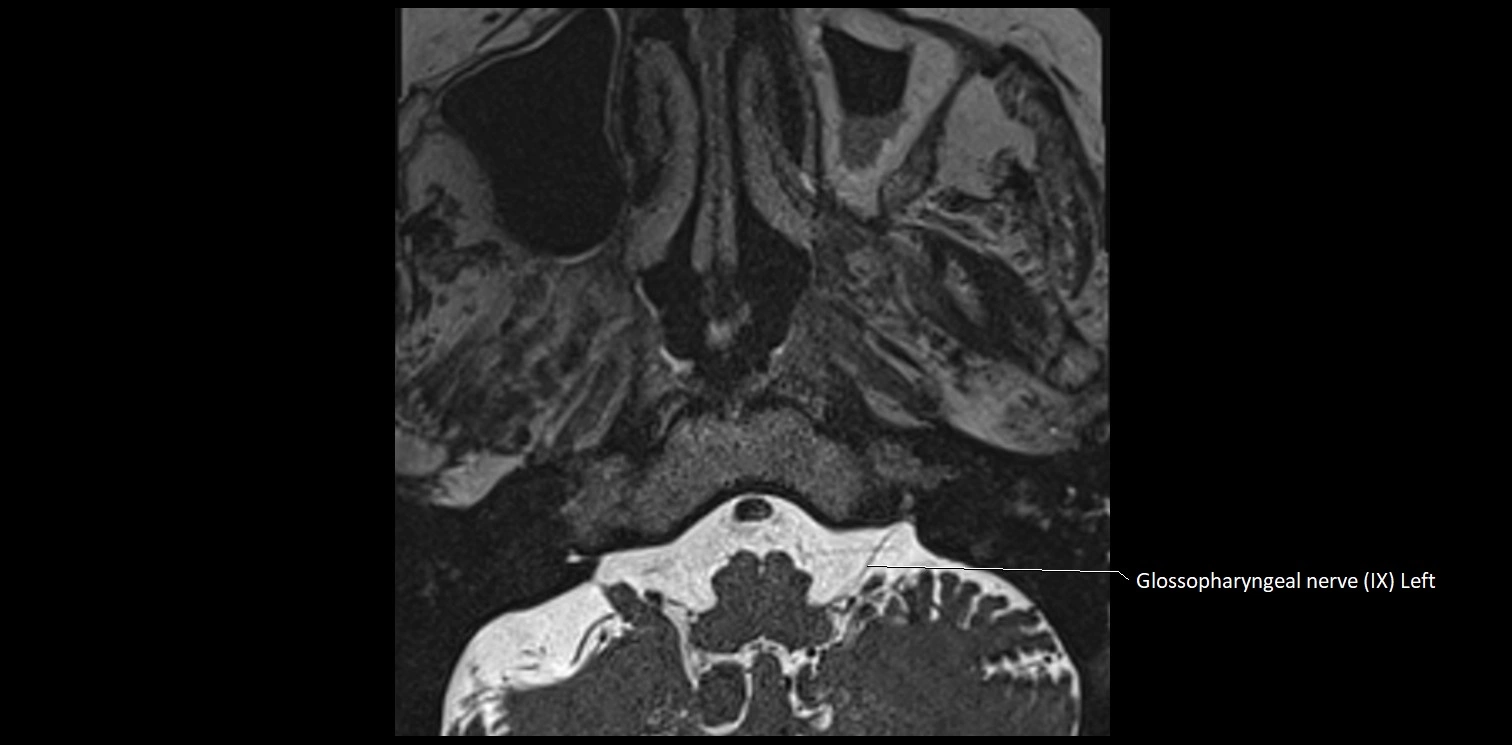

MRI Appearance

• The abducens nerve is a small, thin, linear structure

• Best visualized on high-resolution T2-weighted 3D MRI sequences (e.g., FIESTA or CISS)

• Seen as a hypointense (dark) line running from the brainstem at the pontomedullary junction, traversing the prepontine cistern, and entering Dorello’s canal under the petrosphenoidal ligament, then into the cavernous sinus, and finally the orbit

• May be challenging to visualize in standard MRI due to its small size

• Pathology may be inferred by absence, displacement, or enhancement of the nerve